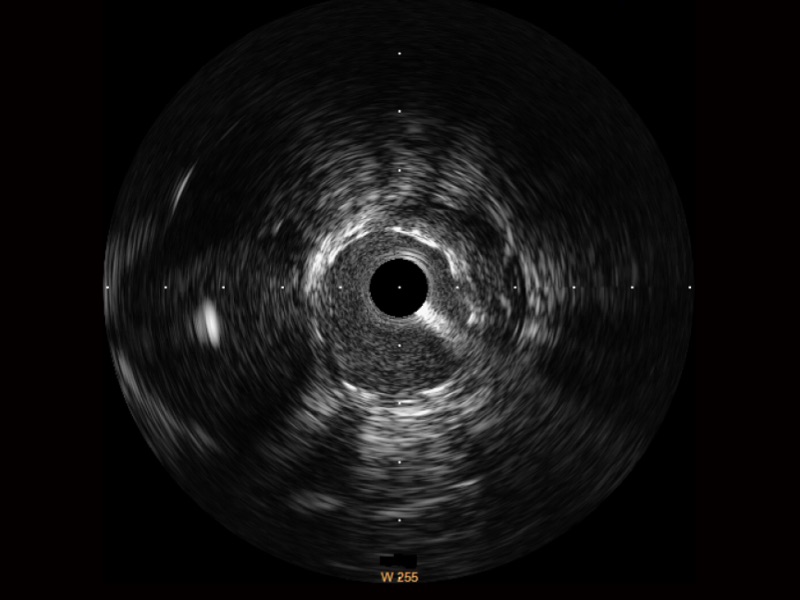

传统IVUS图像

对比传统IVUS导管成像,乐玩lewin国际宽频IVUS图像的近场支架梁显影更细腻,远场中膜外血管仍清晰可辨,兼顾远中近,兼顾分辨力与穿透深度